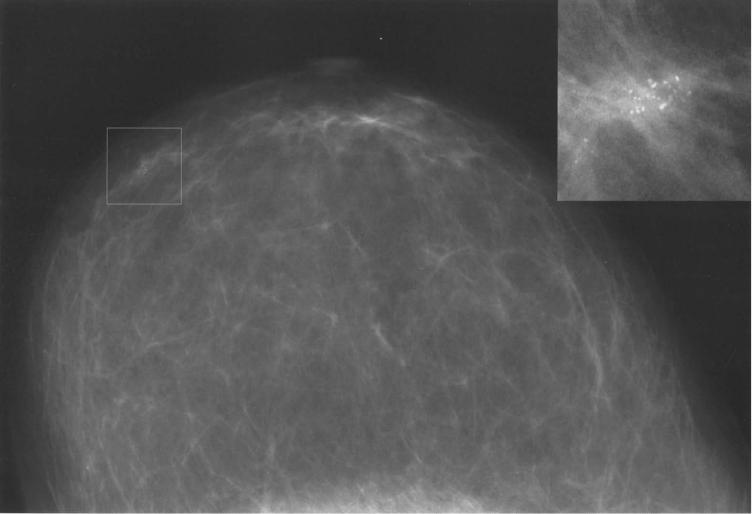

Сделать УЗИ молочных желез можно в качестве первичной диагностики и для уточнения уже предполагаемого диагноза. Метод основывается на способности высокочастотных ультразвуковых волн с различной скоростью отражаться от тканей с разной плотностью.

С помощью ультразвуковой диагностики можно обнаружить следующие заболевания:

- воспалительные заболевания — мастит, абсцессы, лактостаз у кормящих женщин, мастопатии различного происхождения и типа — фиброзно-кистозные, диффузные и пр.;

- врожденные аномалии молочной железы;

- рак;

- кисты и доброкачественные опухоли;

-

кальцинаты.

Для оценки кровотока в тканях молочных желез используется доплерография. Данные, полученные в результате биопсии под контролем УЗ-аппарата, могут сказать о природе и характере образований в молочных железах.